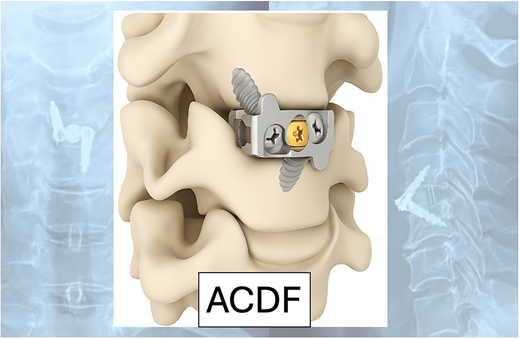

Hình 1. Phẫu thuật lấy nhân đêm và cố định cột sống cổ lối trước (ACDF – Anterior Cervical Discectomy and Fusion).

- Giai đoạn nặng hoặc thất bại điều trị nội khoa: cân nhắc phẫu thuật lấy nhân đệm và cố định cột sống cổ lối trước (ACDF – Anterior Cervical Discectomy and Fusion).